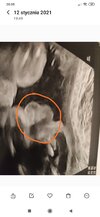

Dziewczyny 31 TC. Lekarz zobaczył jąderka i stwierdził ,że będzie chłopak

chociaż wcześniej twierdził,że dziewczynka ? czy, któraś z Was też tak miała , że widać było jajeczka ale siusiaka brak ? (Zaznaczam ,że mały leżał tyłem) okazało się ,że to faktycznie chłopak? Bardzo chce dokończyć wyprawkę tym bardziej ,że średnio się czuję, a chciałabym też kupić w końcu coś różowego albo niebieskiego bo już frustrują mnie te uniwersalne kolory